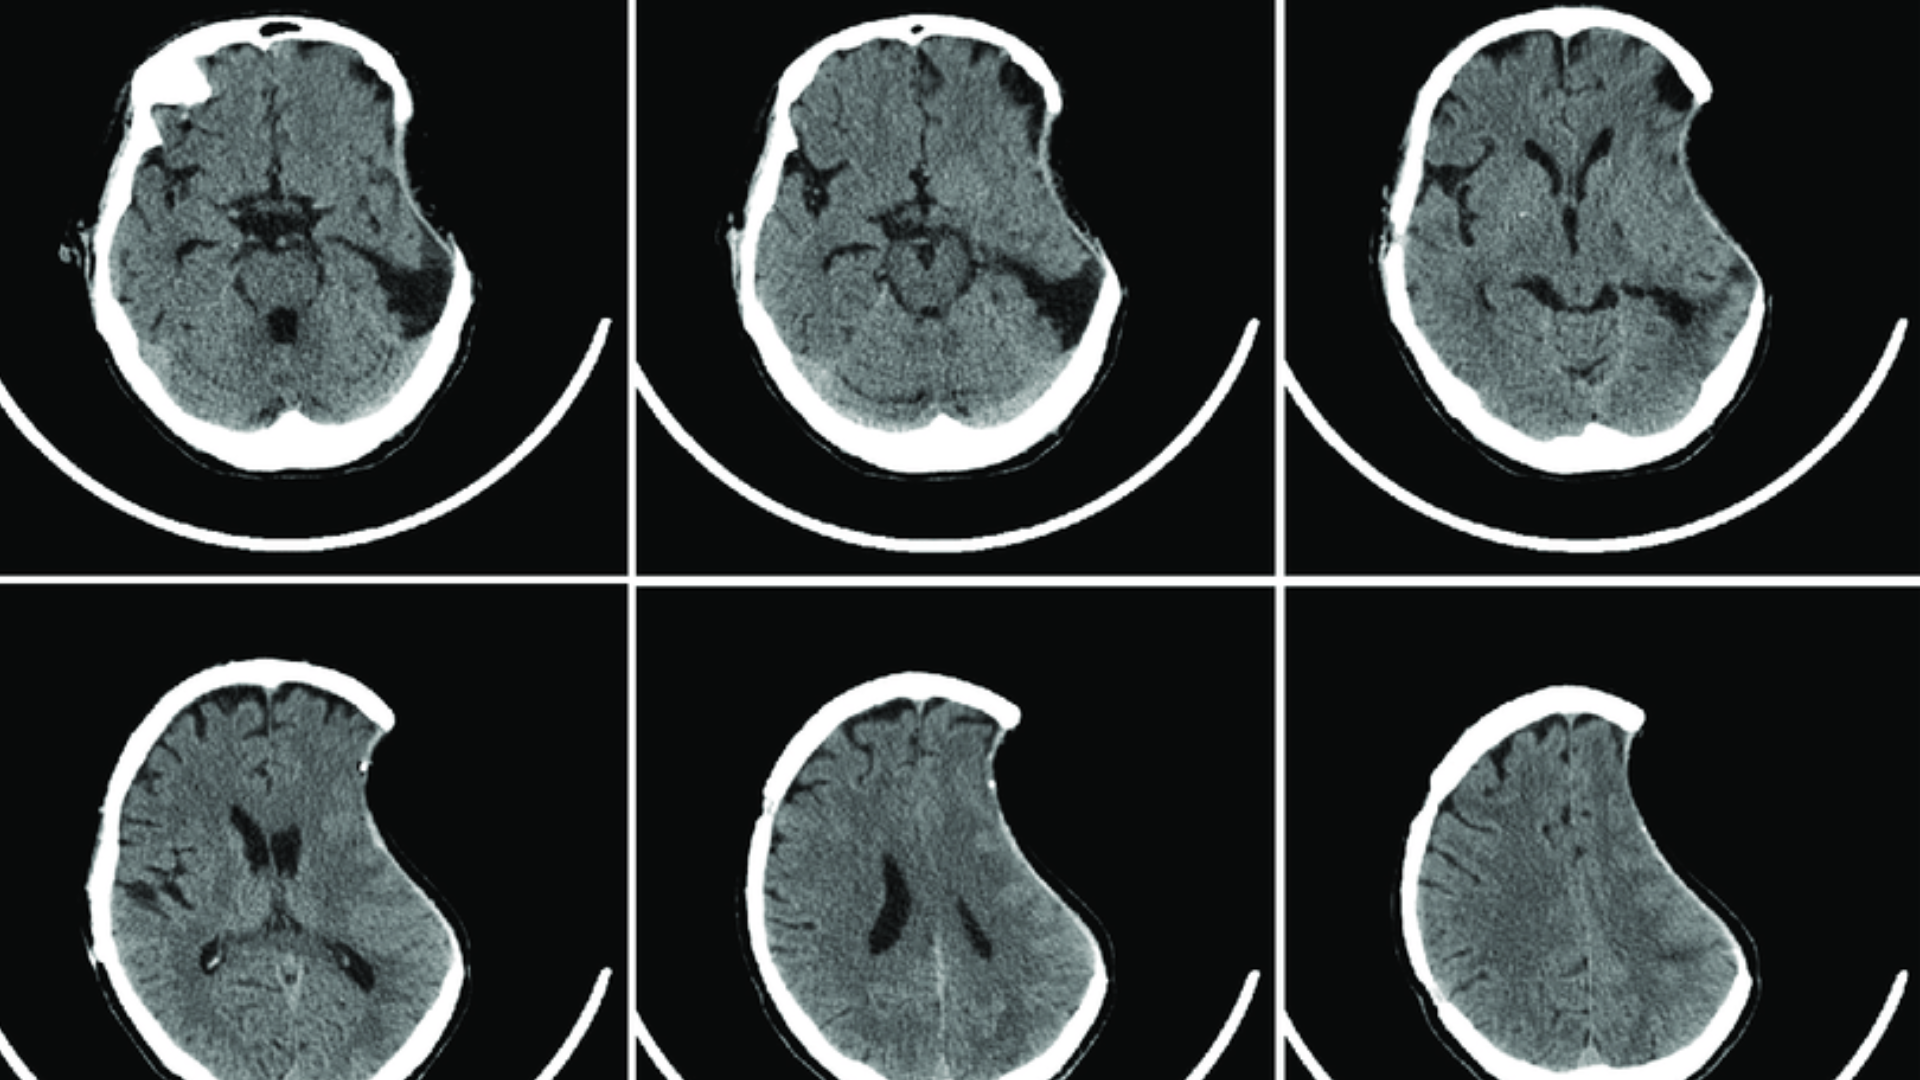

- CT sọ não: Đánh giá cấu trúc xương, phát hiện lún hoặc tiêu xương.

- MRI sọ não: Đánh giá mô não bên dưới nếu nghi ngờ tổn thương thần kinh.

Những kỹ thuật này giúp xác định chính xác nguyên nhân và mức độ nguy hiểm.